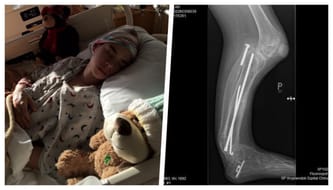

We have taken him to the United States twice already and both surgeries were funded by Polish health care. Dr Paley has lengthened Alan’s tibial bone by 16 cm; he improved the functionality of the knee and ankle, as well as moved the tibia bone back to where it should be. The second trip to the USA would not have been possible without the support of donors (opens a new tab) who helped us to pay for a multi-month stay across the ocean.

In the future, my son will be able to function like his healthy friends, but he needs third surgery in 2019’. We cannot stop halfway and he is still growing. Unfortunately, it's all uphill from here.

We cannot rely on polish healthcare system as they haven’t been approving any requests for the last few years, claiming that this type of defect is curable in Poland. We have many good specialist in Poland, who learn new methods of treatment, but if I had listed to them at the beginning of our journey, my son would have been without one leg and today I wouldn’t have been collecting money for lengthening of his tibial bone, but for new prosthesis. Alan has a chance to walk on his two legs and the only person who has experience in such cases and can help him is Dr Paley.